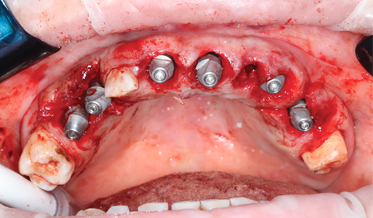

Digital Full-Arch Maxillary Rehabilitation

Isaac Tawil, DDS, MS, Daniel Domingue, DDS, and Scott D. Ganz, DMD